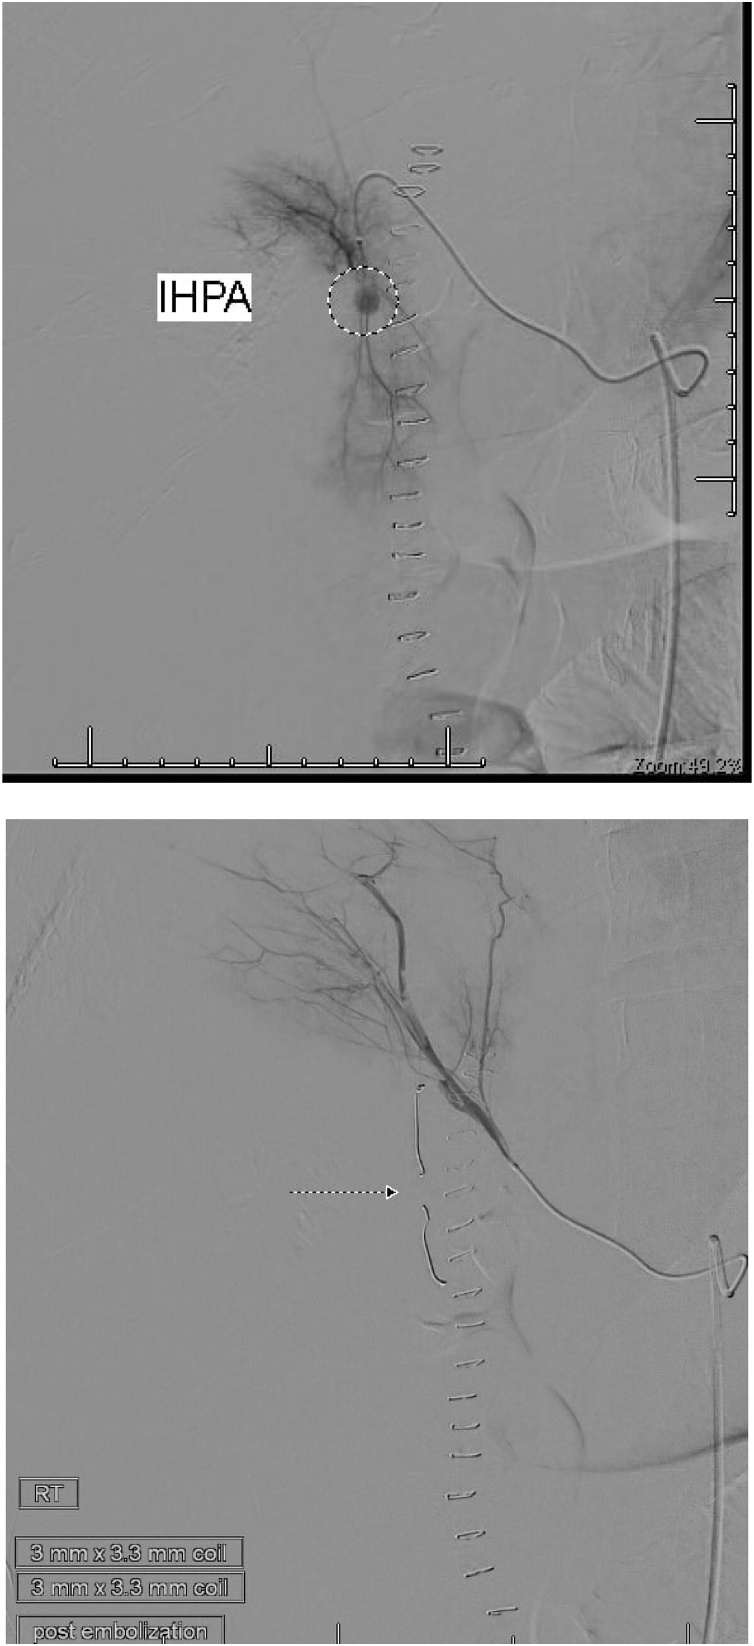

On the tenth postoperative day, the patient complained of a sudden severe abdominal pain. He was pale. The blood pressure was 88/48 mm Hg and pulse rate 142 per minute. The abdomen was tender. CT was done after resuscitation, showed a 24 cm × 13 cm × 8.2 cm heterogeneous subcapsular hepatic hematoma and a 1-cm IHPA (Fig. 9). Superselective hepatic angiography showed an IHPA of the right hepatic artery. The entry and exit points of the aneurysm were successfully embolized with two microcoils (Fig. 10). The patient was discharged home a few days later. No complications were reported during one year of follow up.

Fig. 9.

CECT abdomen showed the IHPA, marked by dotted circle along with subcapsular hematoma.

Fig. 10.

The pseudoaneurysm before embolization; upper figure, and after coils embolization; lower figure.